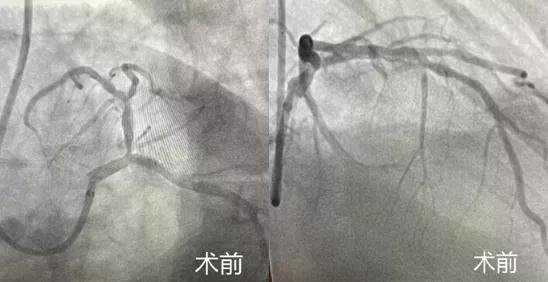

患者老年男性 , 冠脉造影显示前降支开口狭窄90% , 前降支近中段严重钙化 , 狭窄80% 。 该病例手术风险极大 , 重度狭窄且合并严重钙化 , 经介入团队讨论决定进行旋磨治疗 。 手术由雷靖祎主任医师指导 , 刘镇副主任医师操作 , 张磊主治医师协助 。 术中血管内超声(IVUS)探查血管壁360°重度钙化 , 管腔仅2.2平方毫米 , 应用一枚直径1.5mm的旋磨头以18万转/分的速度进行10次打磨 , 成功通过病变后植入2枚支架 , 术后效果理想 , 血管内超声显示支架膨胀良好 。

患者老年女性 , 冠脉造影显示前降支中段90%狭窄合并重度钙化 。 因管腔重度狭窄 , 血管内超声导管无法通过 , 高压球囊无法完全扩张 , 于是立即启动旋磨 。 应用一枚直径1.25mm的旋磨头以16-18万转/分的速度进行12次打磨 , 终于成功开通血管植入1枚支架 。